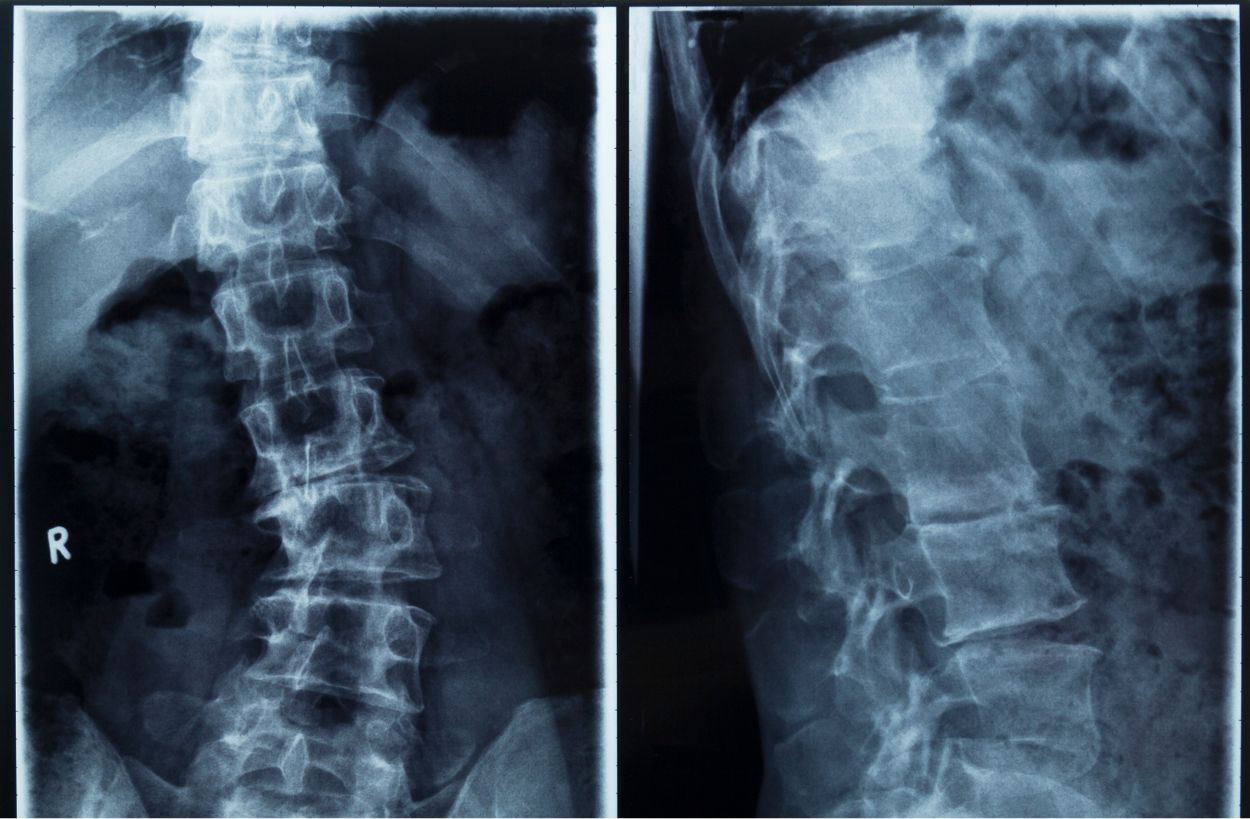

목디스크라는 질환은 디스크(추간판)이라는 척추뼈 사이사이에 위치한 디스크가 변형되면서 경추 신경을 압박하거나 자극하여 목의 통증, 두통, 팔 저림 현상을 일으키는 질환입니다.

목디스크는 허리디스크와 동일한 메커니즘으로 발생하는 척추 신경 질환 중 하나이며, 규칙적인 운동과 올바른 치료가 병행된다면 충분히 개선할 수 있는 질환입니다.

목디스크가 발생하는 가장 흔한 원인은 장기간 잘못된 자세로 인해 척추뼈가 휘거나, 척추 협착증 등으로 인해 디스크가 자극되면서 발생하는 것입니다. 예를 들어 척추 측만증이나, 경추관 협착증 등의 질환이 존재합니다.